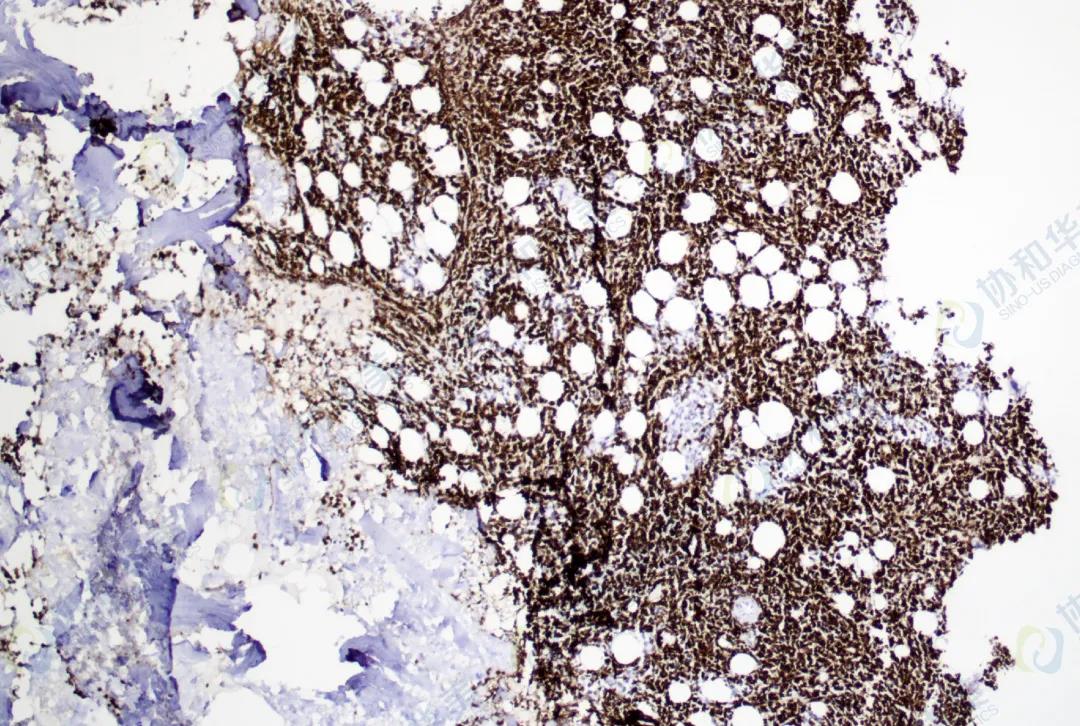

病理

浆细胞白血病